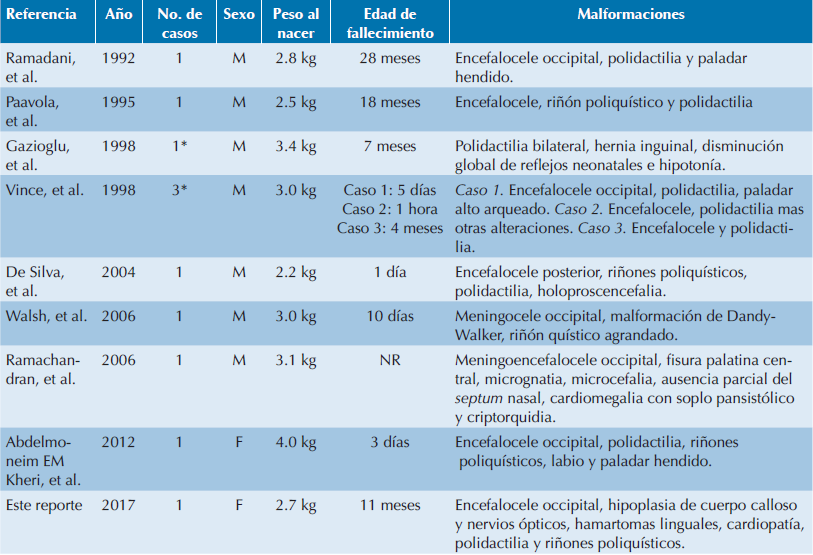

Entre otros defectos comúnmente observados en el sistema nervioso central, en los pacientes con MGS, se pueden incluir: disgenesia rómbica y disgenesia del prosencéfalo, este último puede incluir disgenesia bulbo olfatorio, hipoplasia del nervio óptico, agenesia del cuerpo calloso, holoprosencefalia,1 hidrocefalia y agenesia del cerebelo.12 La paciente presentó: hipoplasia del cuerpo calloso, disminución de volumen de los hemisferios cerebrales, atrofia córtico subcortical moderada generalizada, adelgazamiento del tallo cerebral con ensanchamiento del IV ventrículo e hipotrofia de los hemisferios cerebelosos. Sumado a estos defectos, la paciente también tenía aplasia del nervio óptico bilateral, una afección poco común. En la revisión realizada por Parelkar en 2013 (Cuadro 1) no se describe a la aplasia bilateral del nervio como parte del MGS; sin embargo, ya que en la literatura y en las bases de datos sí hay registros de hipoplasia del nervio óptico12,13 podemos añadir a la descripción del síndrome esta alteración. Se propone que la aplasia bilateral del nervio óptico se debe a la relación que existe entre las ciliopatías y ciertas enfermedades monogénicas degenerativas, muchas de ellas con manifestaciones oftalmológicas y neurológicas.9

Cuadro 1 Casos reportados en la literatura con sobrevida prolongada

NR: No reportada. *Consanguinidad Presente. Modificado de Parelkar et. al 2013.3

El MGS es letal; sin embargo, este caso presentó una sobrevida prolongada, haciéndolo un caso muy relevante ya que hay pocos datos publicados sobre cualquier tipo de nacimiento, muertes fetales y terminaciones de embarazo tras el diagnóstico prenatal. John D. Vince, en 1998, documentó por primera vez una familia de Papúa, Nueva Guinea, con tres bebes que cumplían con los criterios diagnósticos para MGS, pero los dos primeros casos no se documentaron. En 1995, Paavola reportó otro caso compatible con MGS que murió a los 18 meses de vida.22 Hay sólo dos informes de pacientes que sobrevivieron más allá de la infancia y, de acuerdo con Ramadani, existe un reporte de un sobreviviente que murió a la edad de 28 meses.23